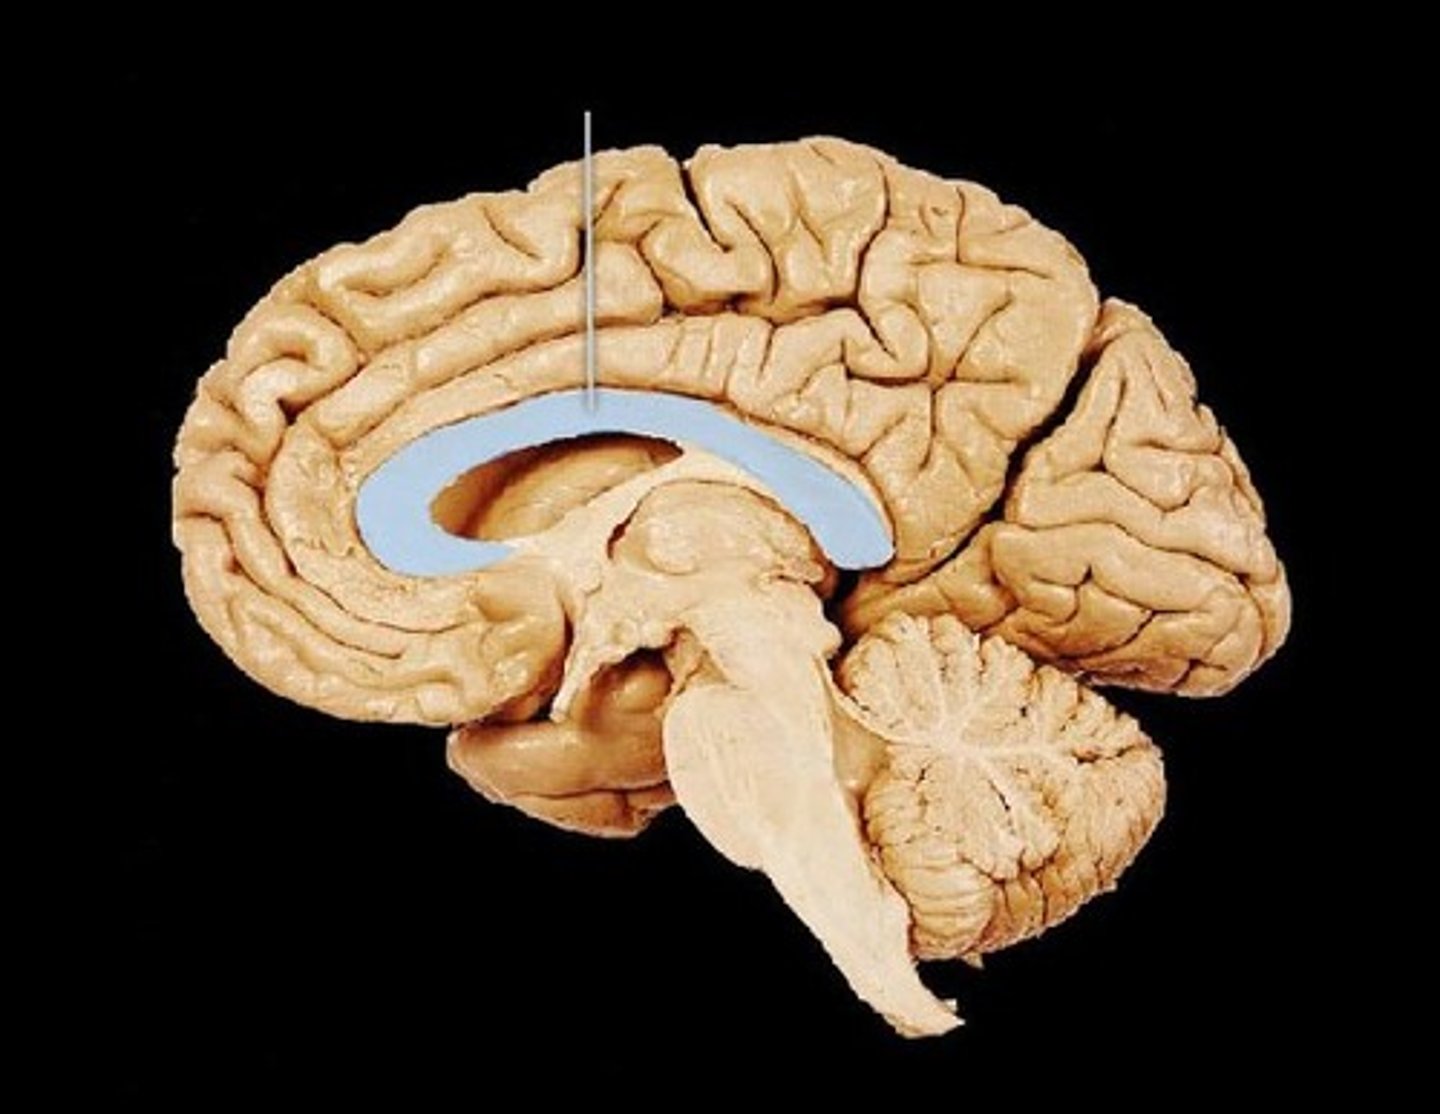

corpus callosum

A broad band of nerve fibers connecting the two hemispheres of the brain.

<p>A broad band of nerve fibers connecting the two hemispheres of the brain.</p>